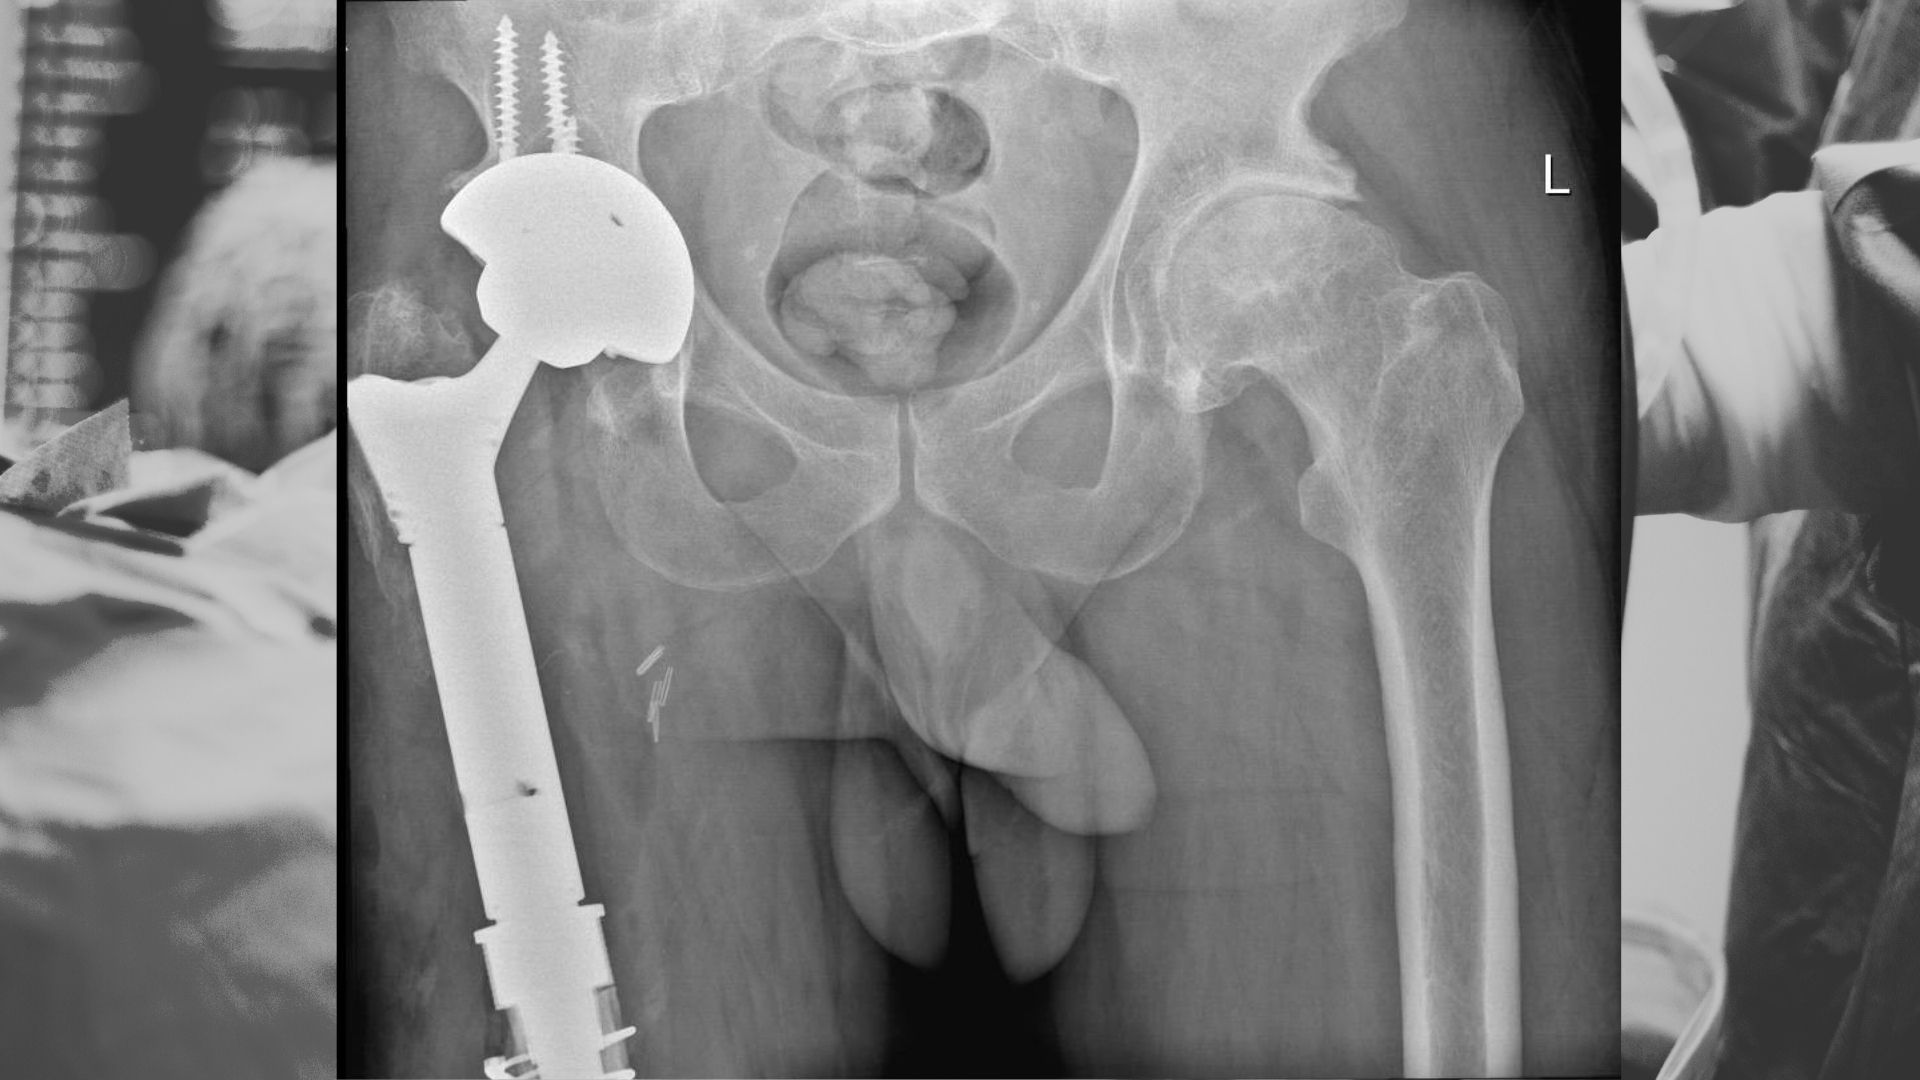

Recent Surgeries

We’ve helped thousands of patients get back on their feet.

Here are some of our successful treatment journeys.

Complex and difficult failed hip replacement surgery revised and reconstructed with an excellent outcome